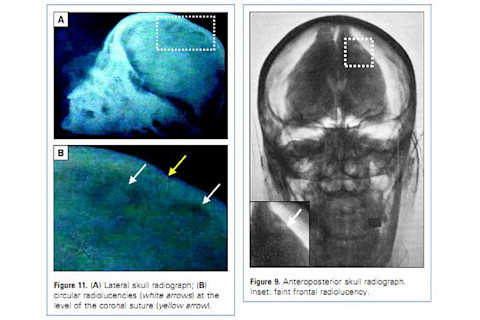

They then point to postmortem X-rays of Peron’s skull which were made public in 1955 to prove that her corpse hadn’t been burned (long story). These, they suggest, show evidence of the kind of burr holes that were used to insert the lobotomy tools –

evitaskull